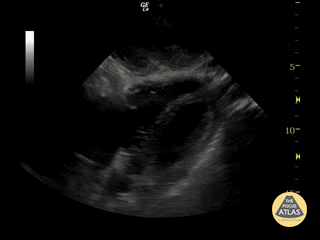

https://www.thepocusatlas.com/left-ventricular-dysfunction

View: Unspecified Parasternal Long Axis Parasternal Short Axis Apical Four-Chamber Subcostal Four-Chamber Subcostal Inferior Vena Cava Right Upper Quadrant Left Upper Quadrant Suprapubic Longitudinal Suprapubic Transverse Subxiphoid Anterior Thoracic Phrenic